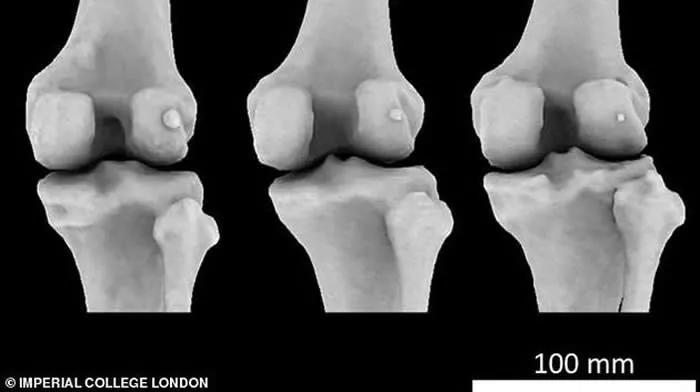

【科学家|人类依然在进化,科学家发现人类正多了块骨头,但这却不是好事情】科学家发现 , 全球40%的人膝盖后方肌腱中长出了一块小骨骼 , 这就是豆骨 。

文章插图

它的直径不足1.3厘米 , 是在我们灵长类祖先身体上发现的 , 它被称为“骨骼阑尾” , 因为它的存在是毫无意义的 。 所以在古猿向人类发展的进程中 , 豆骨已经消失 。

然而研究人员分析了过去150多年进行的2.1万多项科学研究 , 发现目前豆骨在人体存在的概率是100年前的3倍 , 全球40%的人都长有豆骨 。

但是变得更高更重 , 膝盖承受的压力也会越来越大 , 为了更好承受压力 , 膝盖进化出来了新的骨骼 , 那就是豆骨 。 它会在未来逐渐成为人体解剖学中的一个正常变体 。

豆骨在一些哺乳动物之中仍然存在 , 它生长在肌肉的肌腱中 , 就像膝盖骨或髌骨一样 。 在哺乳动物之中 , 它可以帮助帮助减少肌腱内部的摩擦 , 改变肌肉力量 , 或者 , 就像膝盖骨一样 , 增加肌肉的机械力量 。

科学家发现 , 在人类中 , 这一现象在男性中比在女性中更为普遍 , 与年轻人相比 , 年龄较大的人更为普遍 , 而且存在很大的区域差异 , 豆骨在生活在亚洲和大洋洲的人中最常见 , 在北美和非洲的人中最不常见 。

事实上 , 英国五分之一45岁以上人群遭受着这种痛苦 , 他们膝盖长出豆骨的概率是其他年龄段人群的两倍 。 一些专家表示 , 如果发现豆骨 , 就应该尽早移除 。